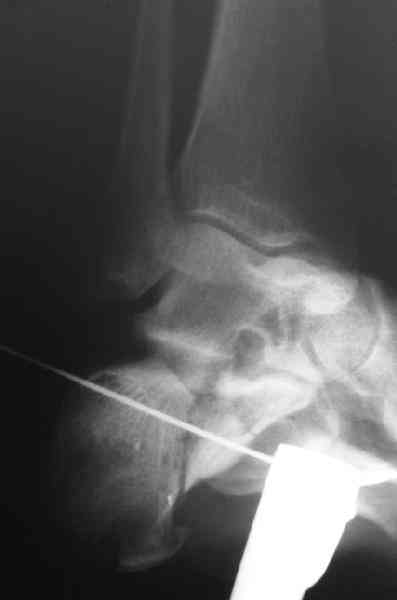

Если я правильно понял, вы хотели спросить: "Что делать с кистой, и как на этом фоне выполнять репозицию и фиксацию перелома?"

Я думаю, что для начала нужно выполнить КТ пяточной кости и определиться с границами полости. Не исключено, что отрывной перелом верхнего полюса бугра носит патологический характер (верхняя стенка кисты).

Its a comminuted one.

I would have a CT prior 2 surgery(If u have to postpone a surgery for it - I would operate without one)

I myself would reduce it with EX-FIX and depending on the result would consider a plate on the table.

MOST OF MY COLLEGUES WOULD OPEN IT LATERALLY( a flap) and having a proper reduction would put a plate.

Если нет опыта в остеосинтезе пяточной пластиной то лучше начать с экскохлеации полости кистозного образования и заполнения его остеоиндукторами Коллапан, Тутопласт, etc.Закрытая репозиция с рентгенконтролем на столе и перкутанная фиксация спицами пяточного бугра с фиксацией в эквинусе могут дать вполне приемлемый результат.

Сустав похоже интактен, киста под вопросом,даже при наличии опыта остесинтеза пластиной, в данном случае выведение правильного угла и фиксация спицами более чем достаточно, да и намного спокойнее сон у хируга.

Перелом безусловно внутрисуставной. Киста-не киста принципиального значения не имеет.